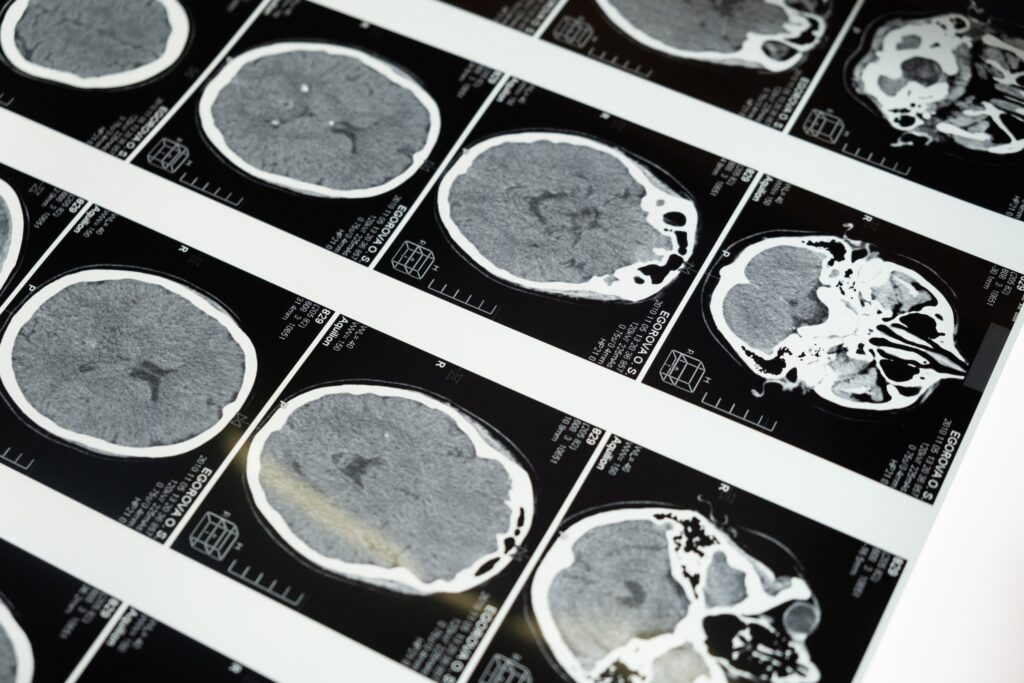

Objektivi kryesor i teknologjisë novatore të Neuralink është të krijojë një implant truri që mund t’u mundësojë individëve të paralizuar të ecin përsëri, duke ofruar shpresë për individët me kufizime të rënda fizike. Ky projekt i fundit synon gjithashtu të kurojë sëmundje të ndryshme neurologjike, duke ilustruar potencialin e jashtëzakonshëm që ka kjo teknologji.

Ndërsa shumë kompani të tjera presin rezultatet e para të kësaj teknologjie, Neuralink qëndron në krye të një epoke të re në teknologjinë mjekësore, duke ofruar një fije shprese për individët dhe familjet e panumërta në mbarë botën të prekur nga ç’rregullimet neurologjike. Miratimi i FDA-së nënkupton jo vetëm një hap të rëndësishëm për Neuralink, por një hap kolosal drejt së ardhmes së neuroshkencës. Vetëm koha do të tregojë se si kjo teknologji revolucionare do të riformësojë mjedisin e shëndetit dhe rehabilitimit neurologjik.